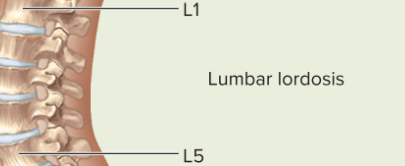

Lumbar curvature

Lordosis, convex anteriorly, curves forward